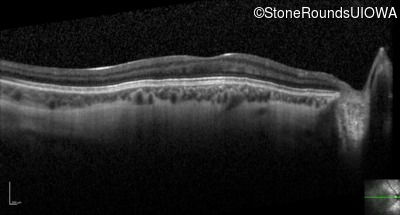

Optical Coherence Tomography - Left - 20/100

Exemplar / OCT Stack

OCT Stack